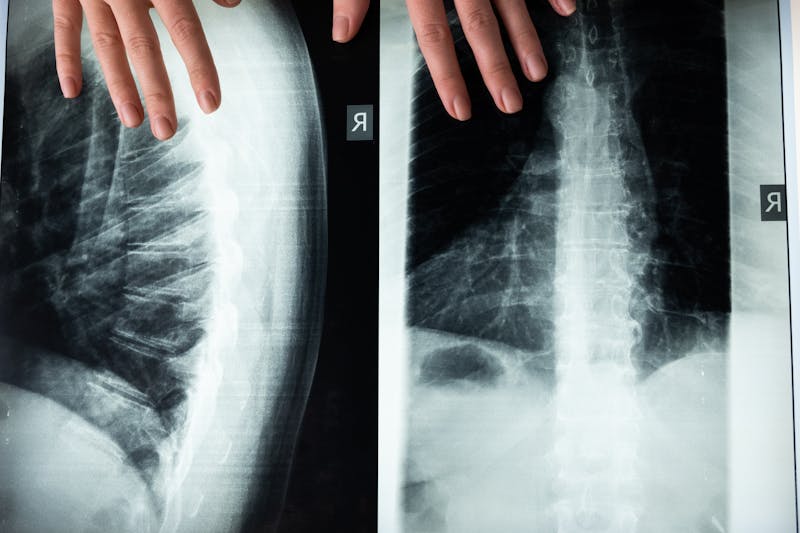

Acesta este probabil cel mai răspândit mit și totodată cel mai ușor de demontat. Doar o parte dintre investigațiile imagistice utilizează radiații ionizante. Radiografia convențională, tomografia computerizată și investigațiile de medicină nucleară fac uz de radiații X sau gamma. În schimb, ecografia se bazează pe ultrasunete, iar rezonanța magnetică folosește câmpuri magnetice puternice și unde radio. Niciuna dintre aceste din urmă două investigații nu expune pacientul la radiații ionizante, motiv pentru care se folosesc preferențial la copii, gravide și la pacienți care necesită monitorizări repetate.

Mai mult, chiar și investigațiile care folosesc radiații au evoluat semnificativ. Aparatele moderne de tomografie computerizată reduc doza de radiații cu 60-80% față de aparatele de acum două decenii, prin algoritmi avansați de reconstrucție și prin protocoale optimizate pentru fiecare tip de pacient și fiecare regiune anatomică. Beneficiul diagnostic depășește cu mult riscul minim asociat unei investigații justificate medical.

Această confuzie apare frecvent la pacienți, mai ales atunci când o ecografie inițială nu evidențiază nicio anomalie. Realitatea este că diferitele tipuri de imagistică oferă informații complementare, nu interschimbabile. Ecografia este excelentă pentru evaluarea organelor abdominale superficiale, a tiroidei și a sânilor la femeile tinere, dar are limite semnificative în vizualizarea structurilor profunde sau a celor înconjurate de aer și os.

RMN-ul, în schimb, oferă rezoluție anatomică superioară pentru țesuturile moi, vizualizează detalii imposibil de evidențiat ecografic și permite caracterizarea precisă a leziunilor descoperite. Cele două investigații nu se exclud reciproc, ci adesea se completează în arhitectura diagnostică modernă.